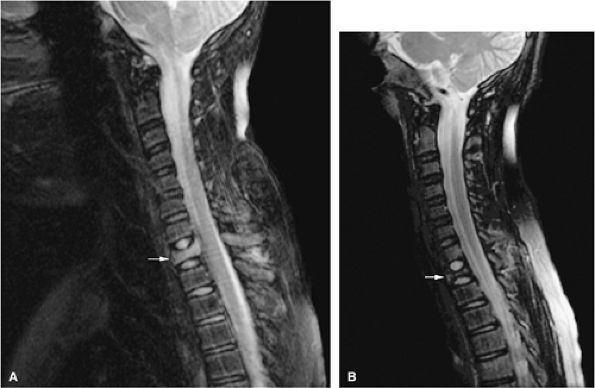

|

FIGURE 13.19 ● Diffuse marrow infiltration of the ankle in a patient with chronic myelogenous leukemia. Sagittal T1-weighted image (A) shows diffuse low-signal leukemic infiltration, which is bright on the corresponding sagittal STIR image (B).

In the acute phase of chronic leukemia, particularly in chronic myelogenous leukemia patients in blast crisis, there is almost complete replacement of both red and yellow marrow areas. The decreased signal on T1-weighted sequences represents replacement of marrow fat by tumor cells, which have a significantly longer T1 relaxation time. On STIR images, tumor cells appear as areas of white on a black or gray background (Fig. 13.19).